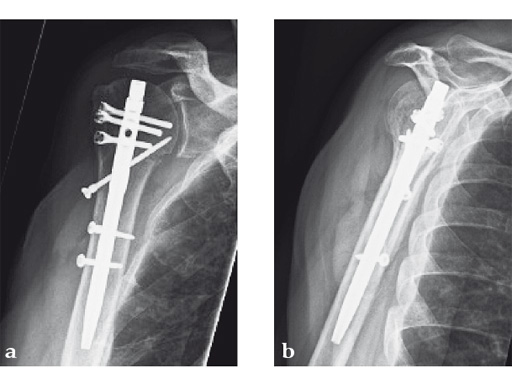

Case 1: A three-part valgus impacted fracture of the proximal humerus in a 47-year-old woman.